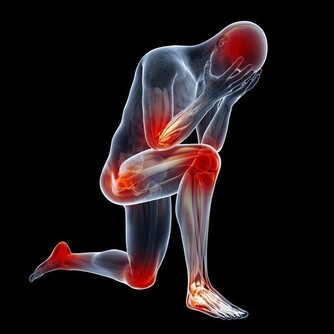

夏季人體易出汗,隨著基礎新陳代謝的變快,營養物質的消耗會增加,加之癌症患者本身的食慾不振,引起營養攝入量減少,容易導致蛋白質和微量營養素(維生素B、維生素C和鋅)的缺乏,飲食中應注意補充。特別是手術後、正在進行放化療的病人,應按照正常的飲食原則盡量予以補充,不能因為治療後產生的強烈副作用而減少飲食。